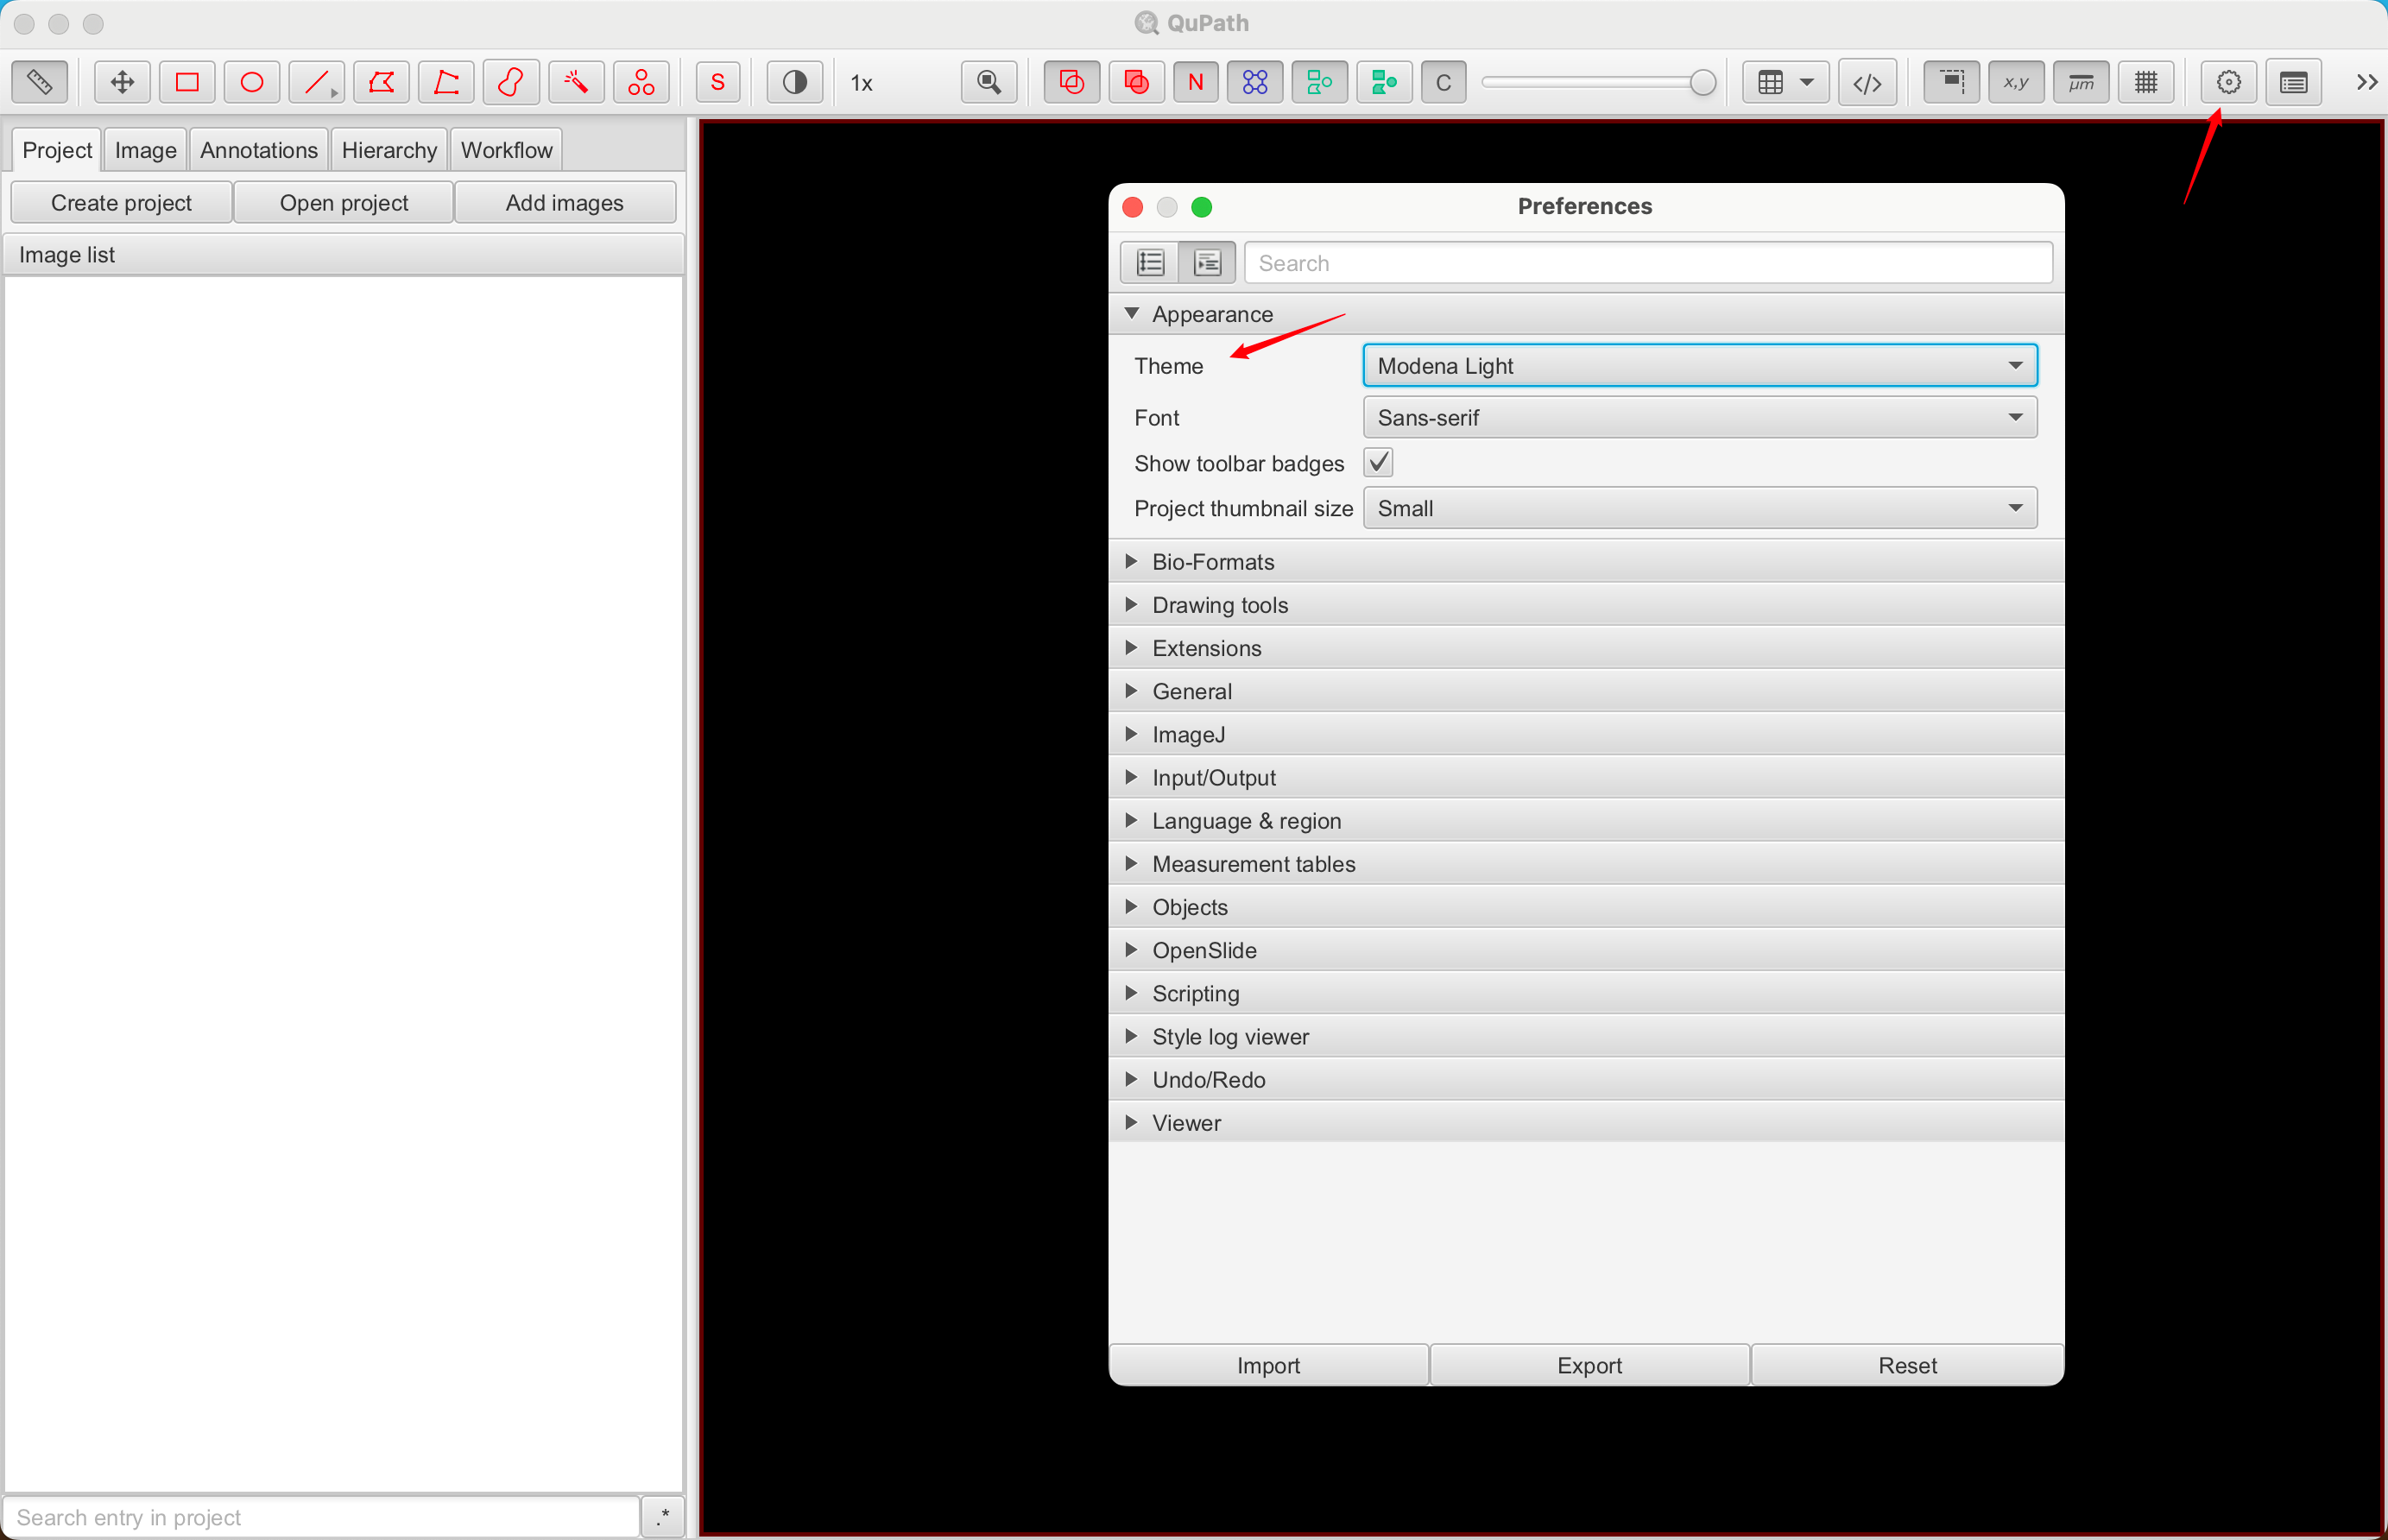

对于那些喜欢在暗模式下使用软件(或想要使用自己的创意主题)的人来说,可以在这里进行更改。此外,还可以检查 QuPath 或扩展的更新,以确保您可以使用最新功能。

如果你想每次打开都看到欢迎界面,可以在Preferences中进行设置。